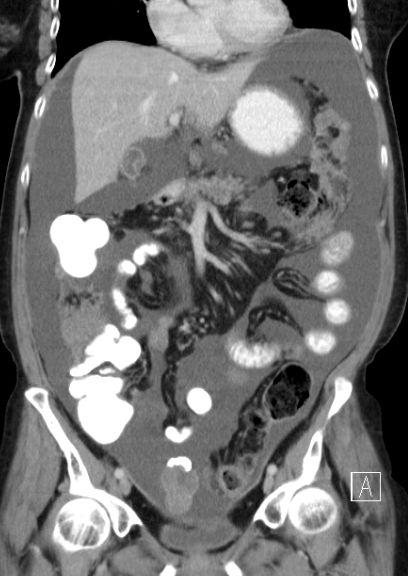

75-jährige Frau mit beiderseitigem Ovarial-Karzinom.

Ausgeprägte infiltration des Netzes und des Peritoneums.